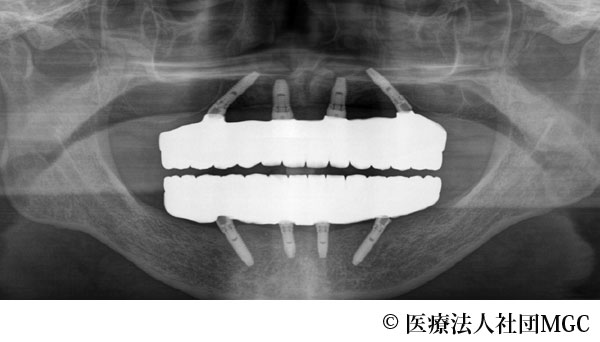

【症例2】上下All-on-4(オールオンフォー)

- 治療後

- 治療名

- 上下All-on-4(オールオンフォー)

- 費用

- 5,888,300円(税込)

- 期間

- 7ヵ月

患者様の症状

総入れ歯が合わず、噛めないとお困りでご来院されました。

治療法

ご相談の結果、患者様の生活の質(QOL)を向上させ、しっかり噛めるように上下All-on-4(オールオンフォー)を行いました。

治療結果

機能性、審美性ともに改善し、満足していただけました。

※治療結果は患者様によって個人差があります。

治療を行う上での注意点(リスク・副作用)

インプラント周囲炎の可能性、まれに歯が欠ける可能性があります。